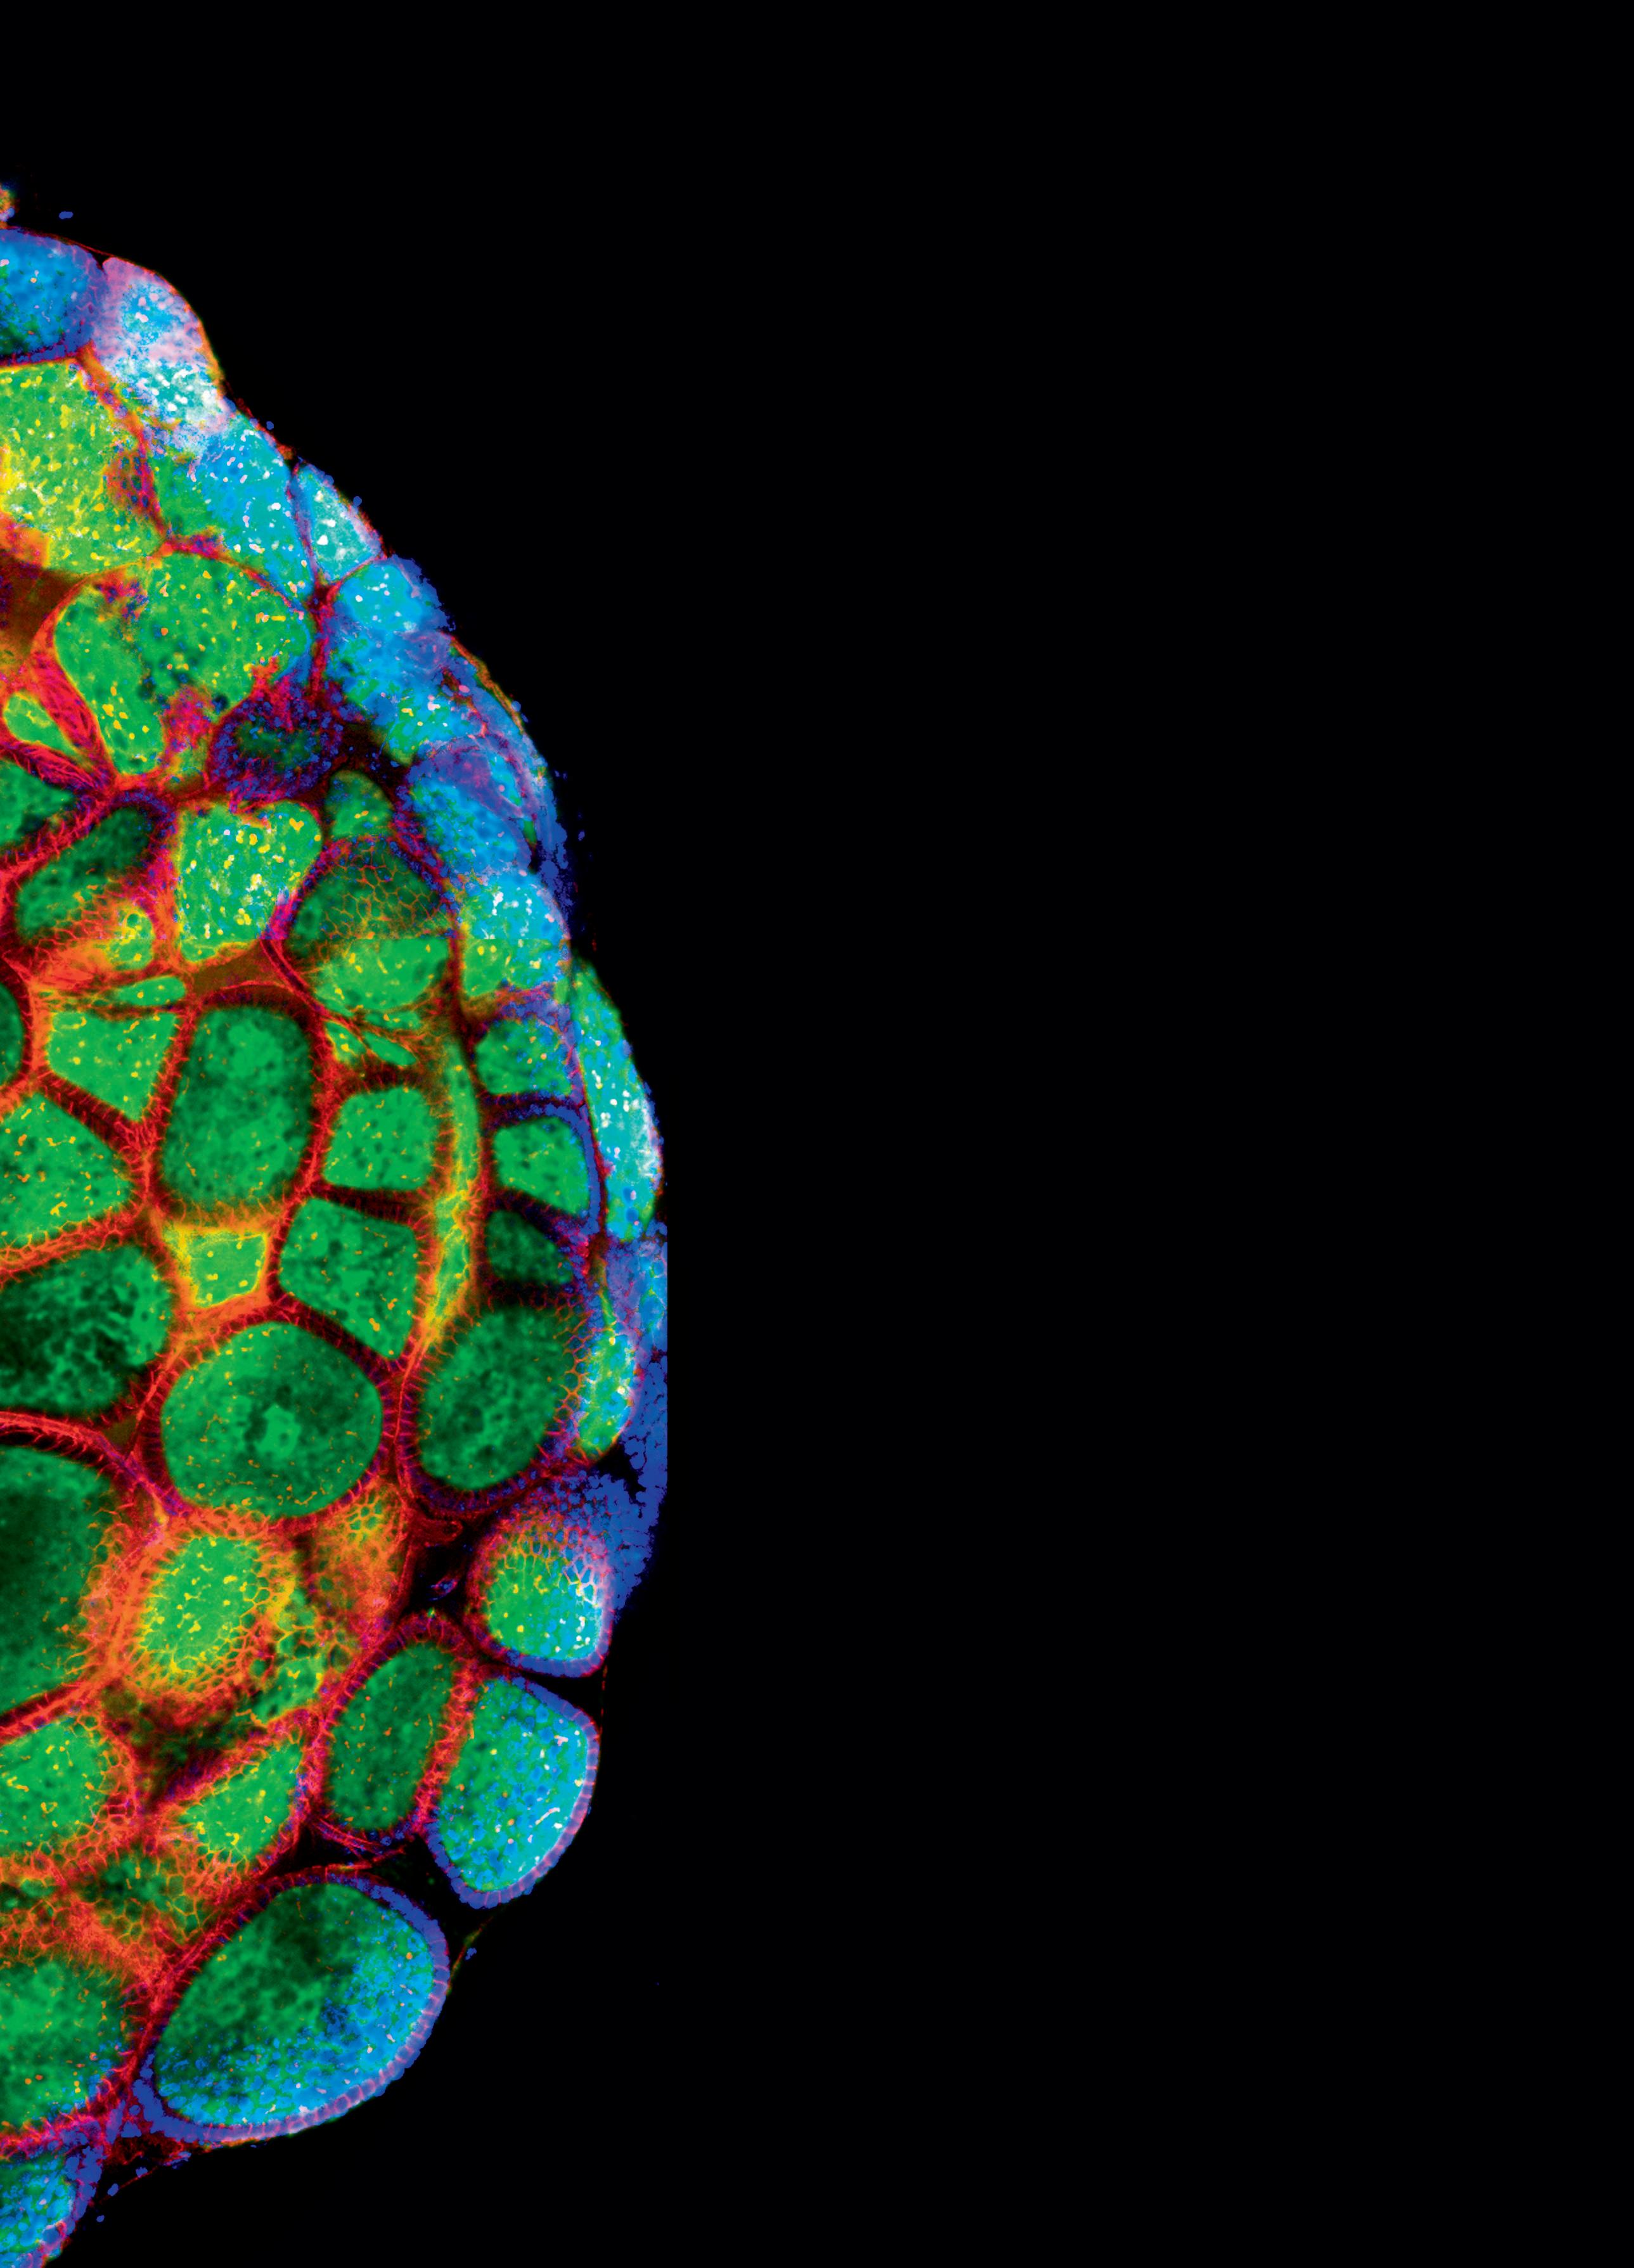

ass die Artenvielfalt in der Pflanzenwelt ein vielversprechendes Reservoir an potenziellen medizinischen stoffen bietet, konnten kürzlich deutsche Wissenschaftler untermauern. Sie untersuchten 26 Pflanzenarten aus dem Jemen und fanden anhand von Zellversuchen bei den meisten antioxidative und antimikrobielle Wirkungen oder einen positiven Einfluss auf das Wachstum von Krebszellen. ajo

Hitze zerstört Tumorzellen. Die Hyperthermie macht sich diese Wirkung zu Nutze. Sie verstärkt die Wirkung von Chemo- und Strahlentherapie, und wird bei der Krebsbehandlung als sanfte Zusatzmethode immer wichtiger.

Was ist Hyperthermie genau und wie funktioniert sie? Es ist schon lange bekannt, dass Krebszellen hitzeempfindlicher sind als gesunde Zellen. Werden sie auf 41 bis 43 Grad Celsius erwärmt, sterben bereits viele von ihnen ab. Helmut Knorr und Volkmar Wirth arbeiten seit März 2009 mit einem hochmodernen Gerät zur Anwendung der sogenannten lokoregionalen Tiefenhyperthermie. Es erzeugt elektrische Felder, die das Tumorgewebe auf 41 bis 43 Grad erwärmen. Diese Wärmeanwendung erzeugt folgende Wirkungen:

l Veränderung an den Zellmembranen der Tumorzellen, es entstehen sogenannte Hitzeschockproteine, die das Immunsystem aktivieren. Krebszellen werden dadurch für die körpereigene Abwehr (wieder) erkennbar, Fress und Killerzellen werden ausgesendet, um den Tumor anzugreifen.

l Die Krebszellen werden empfindlicher für zytotoxische Effekte, die Resistenz der Krebszellen gegen gewisse Chemotherapeutika kann ausgelöscht werden. Dadurch entfaltet die Chemotherapie eine signifikant stärkere Wirkung. Diese Wirkungssteigerung durch die Hyperthermie ist auch für die Strahlentherapie nachgewiesen.

Wenig Nebenwirkungen

Wichtig dabei ist, dass die mittels Hyperthermie erzeugte Erwärmung selektiv, das heisst nur im Tumorgewebe erfolgt. Das angrenzende gesunde Gewebe kann die Wärme durch eine stärkere Durchblutung leicht ableiten und hält seine Temperatur bei rund 37 bis 38 Grad Celsius. Diese Fähigkeit hat das Tumorgewebe aufgrund seiner primitiveren Blutversorgung verloren. Die gestörte Blutzirkulation im Tumorgewebe führt zu einer unzureichenden Wärmeregulierung und damit zu einem Hitzestau, sodass die Wärme ihre